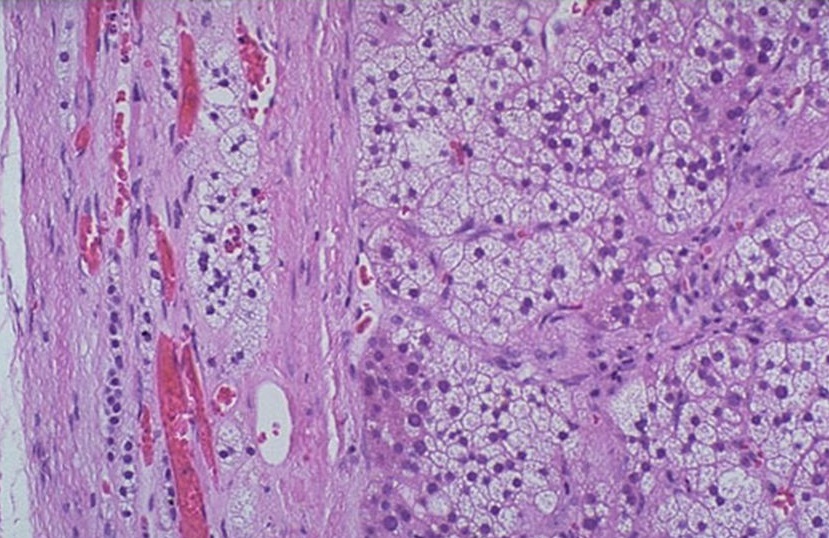

- Адренокортикальная, узловая структура (узелок) в капсуле с жидкостью (светлая);

- Онкоцитарная, состоящая из клеток, имеющая структуру в виде зерна;

- Пигментная, капсула с жидкостью (красная, темно-красная).

В зависимости от цвета клетки делится на:

- Темноклеточная;

- Светлоклеточная;

- Также смешанная.